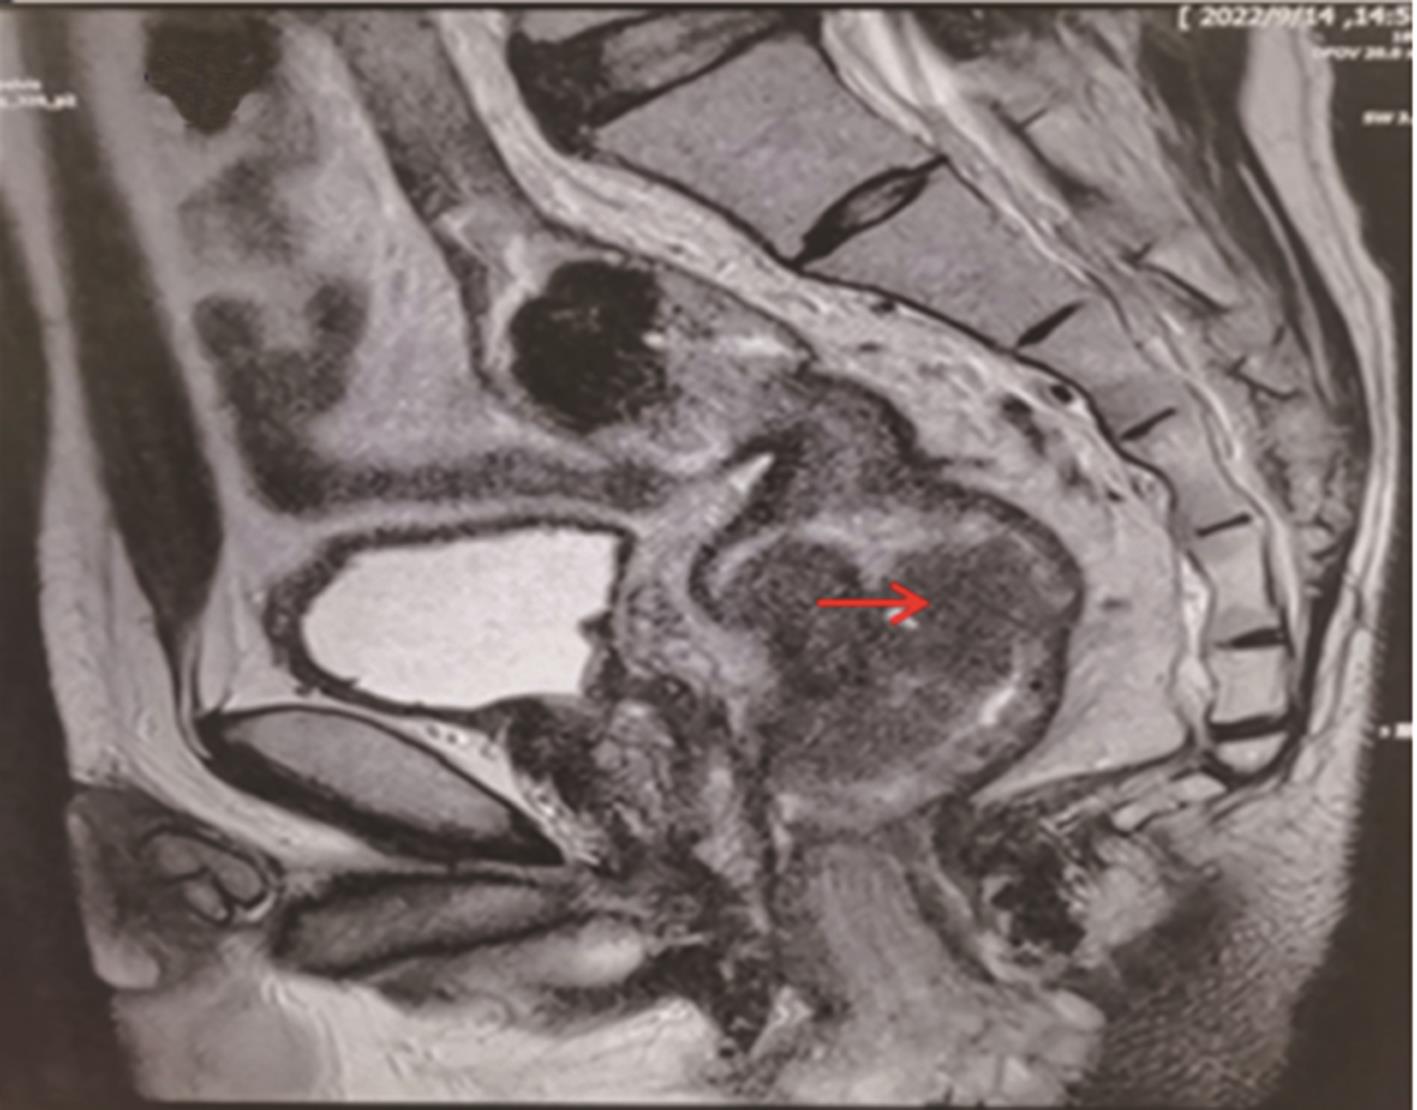

• “镜面人”保留左结肠动脉腹腔镜低位直肠癌根治术1例

2023, 48(7):853-856. DOI: 10.13406/j.cnki.cyxb.003278

摘要 (87) HTML (56) PDF 3.64 M (283) 评论 (0) 收藏